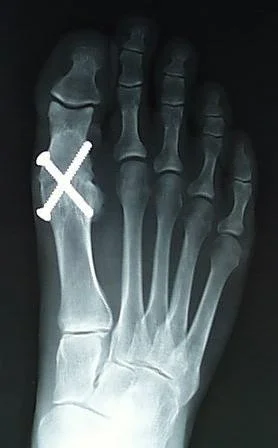

Resection Arthroplasty:

- Remove the articular surface to facilitate movements

- Indicated:

- Old non-ambulatory patient, poor bone and soft tissue quality, Medically unfit & failed multiple reimplantation.

- Contraindication:

- Young active patients

- Disadvantages:

- Short limb, weak muscle, poor function

- Used:

- Hip, Hand & Foot.